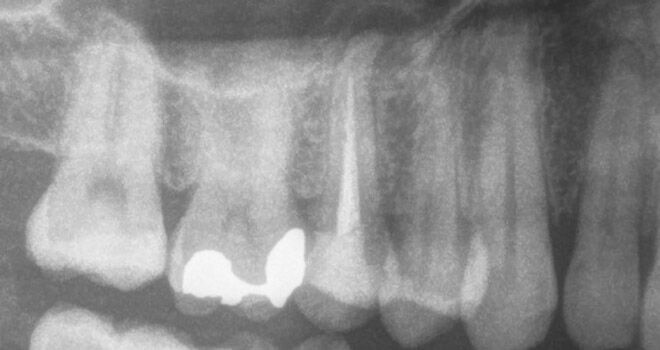

Fall 4: großer interradikulärer Entzündungsherd

Endodontie Fall 4: großer interradikulärer Entzündungsherd

Vor der Behandlung